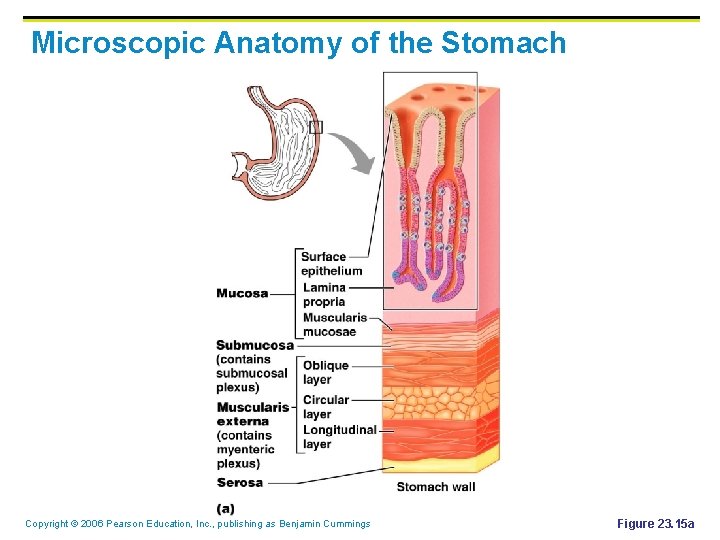

Microscopic Anatomy of the Stomach § Epithelial (tissue) lining is composed of: § § Goblet cells that produce a coat of alkaline mucus Gastric pits contain gastric glands that secrete gastric juice (acidic) and mucus Copyright © 2006 Pearson Education, Inc. , publishing as Benjamin Cummings

Microscopic Anatomy of the Stomach Copyright © 2006 Pearson Education, Inc. , publishing as Benjamin Cummings Figure 23. 15 a